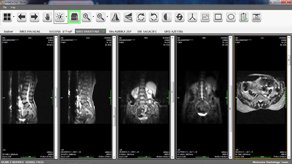

Brand new Workstation for all your radiology needs.

Intelligence lenses on screen to read all images.

World class Kins PACS system with affordable cost.

Art of imaging with proven idea to increase care on patient and revenue.